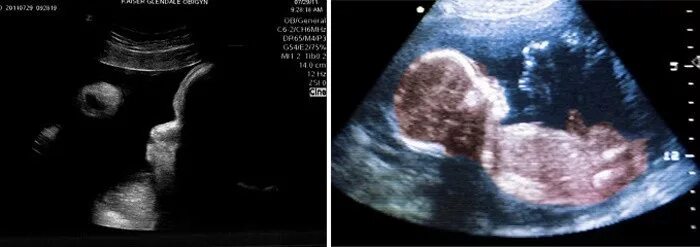

31 неделя беременности тянет